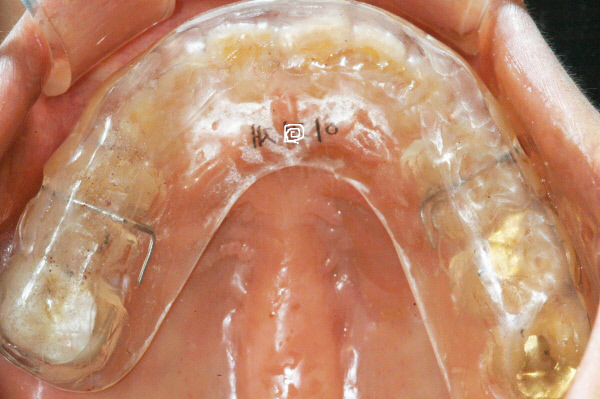

구강내 아래턱 치아에 착용한 CBK스플린트. 정기적으로 치과에서 미세한 조정을 받아야 완벽한 교합 안정이 이뤄진다. 교합이 틀어지면 근육의 왜곡이 일어나면서 두개골이 틀어지고, 뇌와 척수에도 영향을 미치게 된다. 즉 치아가 마모되고 틀어지면서 그 영향을 두개골에서 같이 받고, 이것이 전신건강과 면역시스템에도 영향을 주게 된다는 게 최 원장의 설명이다.